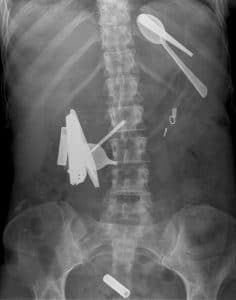

Στον πεπτικό σωλήνα μπορεί να βρεθεί μία πλειάδα αντικειμένων, όπως: κέρματα, κλειδιά, ξυραφάκια, τσιμπιδάκια, οδοντοστοιχίες, μολύβια, κουμπιά, βελόνες, παραμάνες, καρφίτσες, μαχαιροπήρουνα, clips, μπαταρίες, καλώδια, κομμάτια γυαλιού, θερμόμετρα, κόκκαλα, κουκούτσια φρούτων, βλωμοί κρέατος, πιλήματα, χολόλιθοι κ.ά.

Στομάχι: Τα ξένα σώματα που συνήθως αφαιρούνται από το στομάχι είναι τα κέρματα, τα μεταλλικά σώματα και τα σκεύη σιτίσεως (μαχαίρια, κουτάλια, πιρούνια). Μεταξύ των ασθενών πλειοψηφούν αριθμητικά οι κρατούμενοι φυλακών, οι οποίοι, αφενός, με την αυτοκαταστροφική τους συμπεριφορά επιδιώκουν ευμενέστερη μεταχείριση και, αφετέρου, υποβάλλονται σε ενδοσκόπηση για να τους χορηγηθούν ενδοφλέβια διάφορα φάρμακα, που έχουν ηρεμιστική και υπναγωγό δράση. Ακολουθούν οι αλκοολικοί που διατελούν σε κατάσταση μέθης και οι ψυχωσικοί ασθενείς. Τα παιδιά συνήθως καταπίνουν ξένα σώματα από περιέργεια. Επίσης, έχουν τη συνήθεια να βάζουν τα ξένα αντικείμενα στο στόμα τους και να τα καταπίνουν ακούσια.